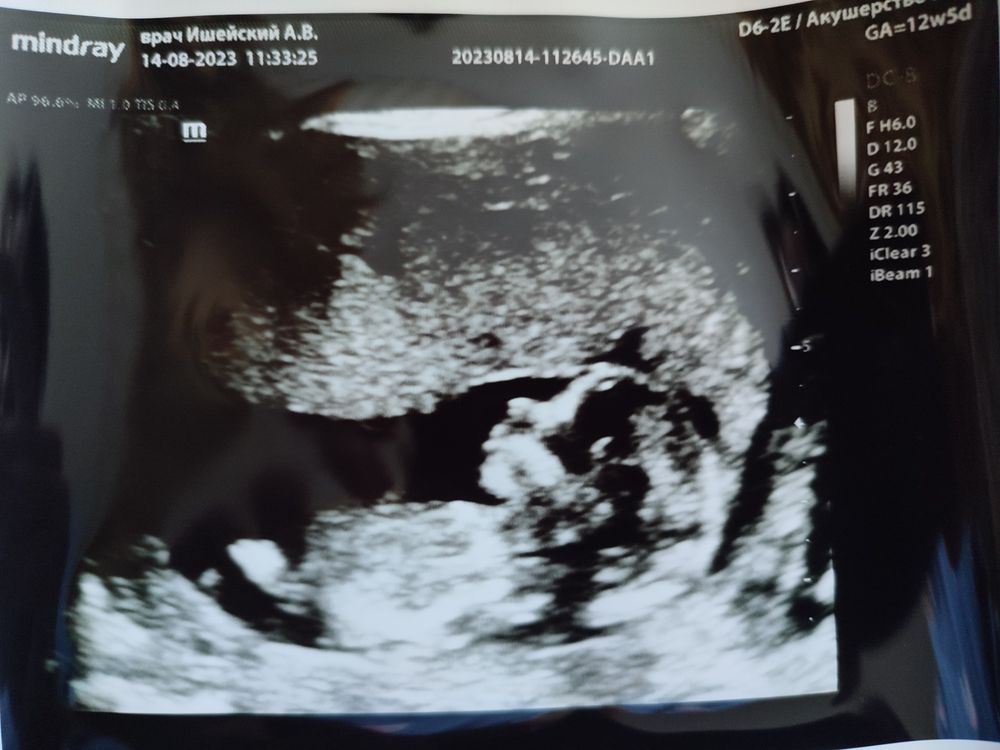

Прошли сегодня 1 скрининг!

Само УЗИ норм, всё в порядке, теперь остаётся ждать результаты крови, через 2-3 дня. Малыш, как всегда, по развитию на неделю опережает ☺ Вовремя пришла. Хорошо, что сделала платно, пораньше (стоимость 3400), т к уже развитие на 13,5 недель. Через пару дней было бы уже не информативно.

Похож на пацана, лобастый. А я хотела девочку 🥺 Рано ещё, конечно, судить о поле, но почему-то кажется, что это мальчик.